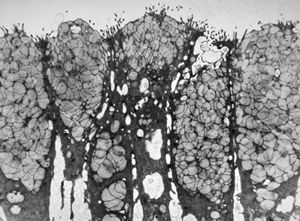

normal mucosa - duodenum - enterocytes and goblet cells